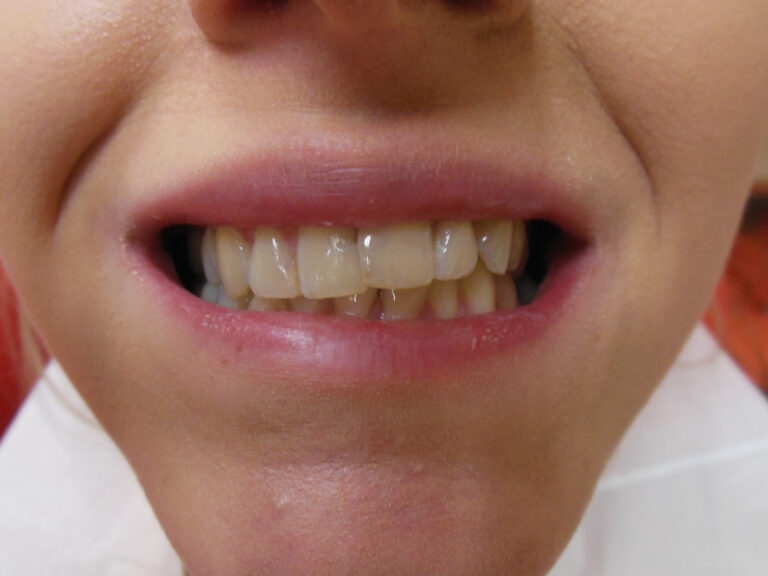

Ortodoncja CBCT

Leczenie chirurgiczno-ortodontyczne wad zębowych z zastosowaniem tomografii spiralnej CBCT w naszej klinice.